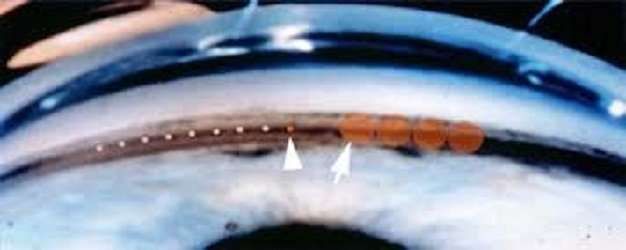

Why does this disease occur? What is wrong with the eye? At the junction of both the cornea and the iris is formed a sieve called the trabecular meshwork. The picture below shows this sieve. In different patients, due to various reasons, the holes of this sieve become closed, which obstructs the drainage of aqueous…

Why does this disease occur? What is wrong with the eye? There is a filter at the junction of the cornea and the iris. It is forms a sieve which is called the trabecular meshwork. There is a system at this place that drains the material from the eye to the blood vessels. For various…

This laser machine is used to treat Narrow angle glaucoma. After-cataract which develops in eyes which have been operated for cataract.. In the following picture glaucoma is being treated. یہ لیزر مشین جسے Yag laser کہتے ہیں درج ذیل مقاصد کیلئے استعمال کی جاتی ہےَ: نیرواینگل گلوکوما کے علاج کیلئے۔ اس کے ذریعے آئرس میں…